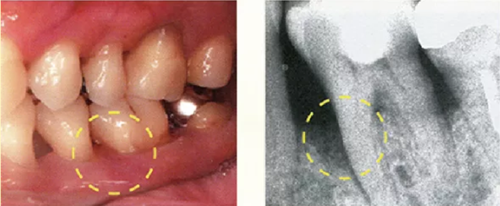

牙周探診在掌握眼睛看不到的部分的狀態(tài)方面,是非常重要的一個(gè)檢查。參考X片進(jìn)行探診,可以立體掌握該檢查部位。

然而X片中無法看到所有信息。魚食,牙周探針的工作尖需要像步行一樣在袋底走動(dòng)運(yùn)用步行式探診法可以更準(zhǔn)確掌握該部位的狀況。

● 僅有X片,無法掌握到牙周袋底的狀況嗎

牙周病即使是在同一口腔內(nèi),每顆牙齒、牙齒的每個(gè)面惡化程度都不相同,有部位特異性。因此,牙周病的檢查不是要看全體的進(jìn)行程度,而是有必要對(duì)逐個(gè)面、逐個(gè)點(diǎn)進(jìn)行檢查。

如果在對(duì)哪個(gè)部位進(jìn)行到什么程度沒有預(yù)想的狀態(tài)下進(jìn)行探診,由于復(fù)雜的根面形態(tài)和牙周狀態(tài),無法正確插入探針、被牙結(jié)石擋住、遺漏等就很容易發(fā)生。

因此,在檢測(cè)牙周袋深度時(shí),通過 X 片確定牙槽骨的狀態(tài)、根的形態(tài)、牙結(jié)石的附著狀態(tài)等,在腦中有一個(gè)大致的印象,應(yīng)該可以很大程度上減少漏檢。

僅通過口腔視診是無法看出何處有骨吸收的。通過拍攝的牙片,可以一定程度上掌握牙槽骨吸收的情況。

如果觀察X片后預(yù)想的狀態(tài)和牙周探診分析出的狀況有很大差異,就需要再次注意此部位并重新做一次牙周探診。